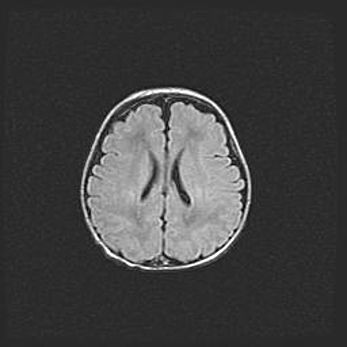

Церебральная ишемия II.

Возраст: 5 дней

Вес: 3400 г

Пол: женский

Окружность головы: 35 см

Срок гестации: 39 недель

Церебральная ишемия – это заболевание, характеризующееся недостаточностью (гипоксией) либо полным прекращением (аноксией) снабжения мозга кислородом по причине закупорки одного или нескольких сосудов. Это приводит к  что метаболическим расстройствам различной степени тяжести в тканях головного мозга, развитию коагуляционных некрозов и гибели нейронов.